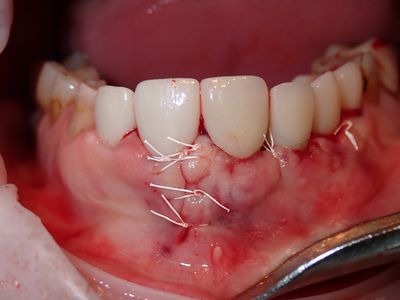

implant was placed and loaded. Pt has pain to tapping implant crown, no other symptoms, esthetics are acceptable. Scan shows implant out of bone buccal. discussion on flap design, started with a small flap but with amount of bone loss, access was key, dropped a vertical. thorough cleaning around implant. grafted site with sticky bone from equal amounts mineralized cortical allograft, xenograft and synthetic bone. Collagen membrane soaked in prf fluid placed defect with 4 membrane tacks. fibrin membrane used overtop. Will assess symptoms in 5 months